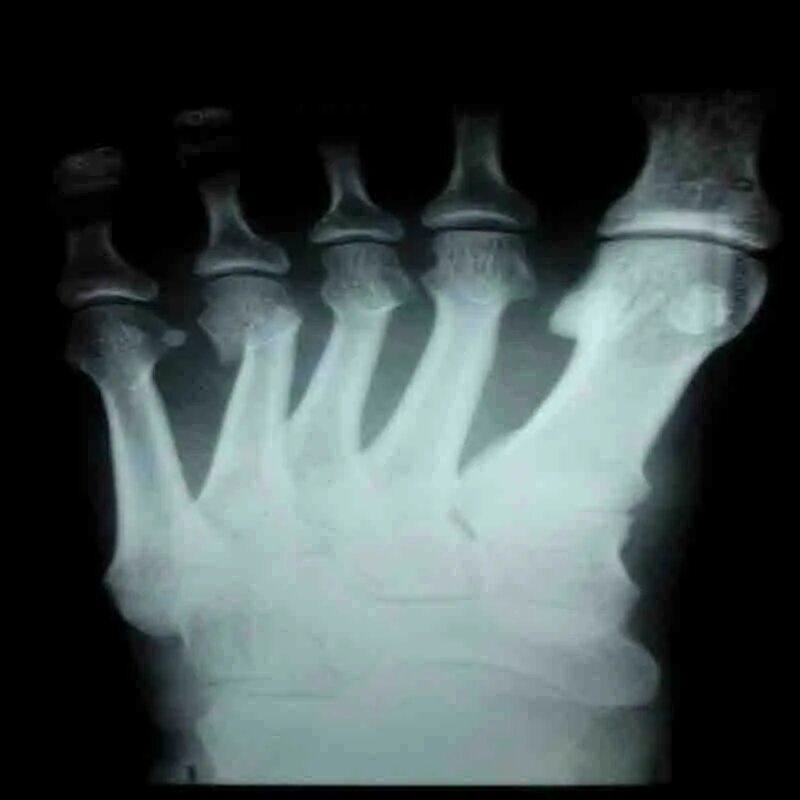

Закрытый перелом пальцев стопы мкб 10